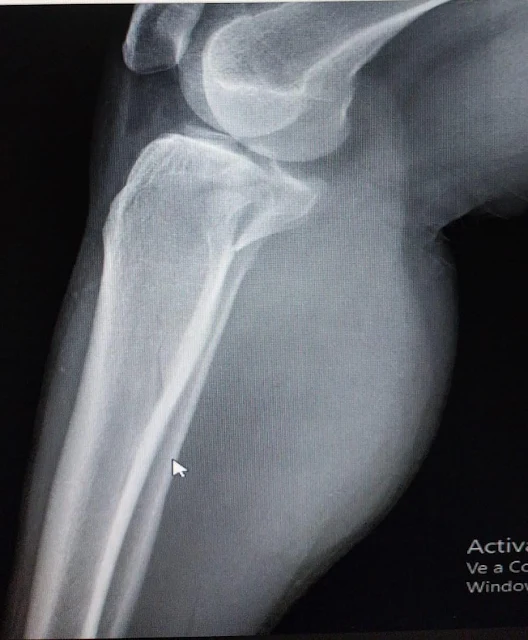

Su hija contó a JUNIN24 que "A mi mamá la chocaron el 1ro de agosto, tres chicos que iban en moto sin luz, sin freno, sin casco, sin seguro, sin nada, llamaron a la ambulancia y de ahí brillaron por su ausencia(es gente que me conoce a mí y a mí familia). Mí mamá ahora esta enyesada, con una fractura de platillo y tibial, tenemos que tratar de que se opere antes de que el hueso se llegue a soldar, ya que sino después tienen que volver a romper todo para poner las prótesis; estamos en espera de las prótesis pero el estado no está mandando hace más de tres meses, no podemos esperar tanto ya que la perjudica a mí mamá, porque sufre de diabetes e hipertensión también".

2Estamos tratando de juntar la plata así que si alguien puede colaborar con algo de dinero, lo que puedan, todo sirve o cosas para poder armar una rifa, se los agradecería muchísimo, quienes no puedan colaborar por favor me ayudenme a difundir para poder conseguir el dinero que necesitamos. Las prótesis nos salen casi 1 millón, mañana me traen el presupuesto impreso así pueden corroborar que es realmente para esto, pero les dejo unas fotos para que vean y cualquier cosita por favor escríbanme", contó su hija.